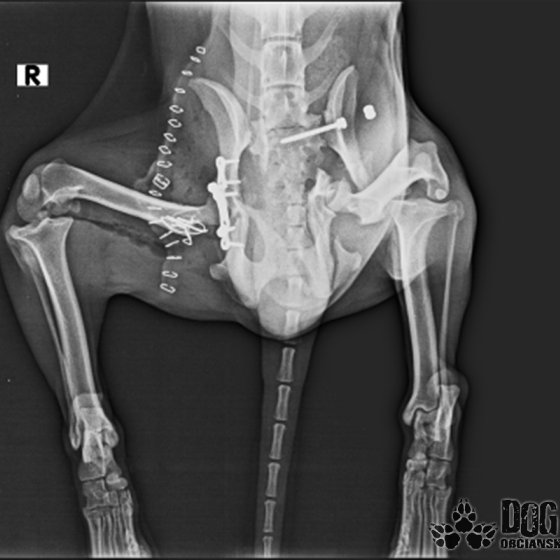

Vianoce nám klopú na dvere a mali by to byť sviatky radosti a pokoja. No u nás nebudú a pre malého Jamesa už vôbec nie. Malého Jamesa sme prijali s mnohonásobnými fraktúrami panvy. Presnejšie, s obojstrannou iliosakrálnou luxáciou/fraktúrou, viacnásobnou fraktúrou panvy, vrátane fraktúry kranialneho acetabula obojstranne. Áno, znie to hrozivo a keď si pozriete snímky z RTG, bude to ešte hrozivejšie (ďalšie snímky ešte doplníme).

Čakali ho teda štyri, veľmi náročné ortopedické operácie, takže sa musel trocha posilniť. Do starostlivosti si ho vzala MVDr. Panyi Terzieva a 17.11. mohol absolvovať prvú operáciu. V "prvom kole" krpec zvládal anestézu tak dobre, že sa rovno mohli spojiť dve operácie a tak sa celá ľavá strana dala do poriadku. Zostal samozrejme naďalej hospitalizovaný. Ďalší zákrok sa naplánoval na 20.11. a našťastie opäť všetko prebehlo hladko, a zoperovala sa celá pravá strana(nechceme sa dlho rozpisovať, prikladáme lekársku správu). James bol prepustený 24.11. ako chodiaci pacient a bez problémov ovládal aj vylučovanie! Je to priam zázrak, za ktorý opäť vďačíme MVDr. Vatolíkovi a jeho teamu.